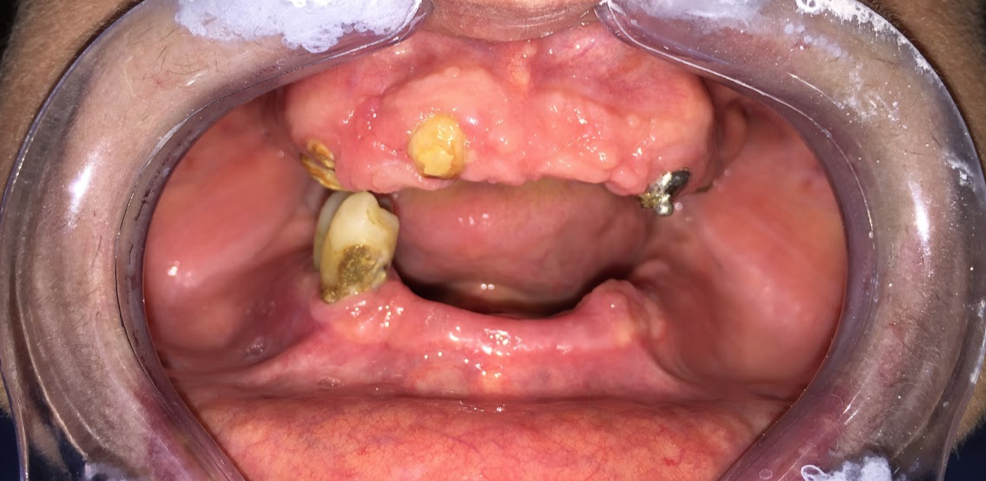

II fase o tempo dell'inserimento degli impianti: in questo tempo terapeutico si procede all’inserimento di impianti in titanio nelle zone edentule delle ossa mascellari e/o mandibolari. Grazie alla particolare tipologia di impianti specifici e al corretto posizionamento degli stessi, è possibile procedere direttamente con la fase protesica. L’intervento sarà completamente indolore grazie anche all’ausilio della sedazione cosciente (previa valutazione medica del nostro anestesista).

III fase, posizionamento della protesi sugli impianti: fase chirurgica: con il supporto del Laboratorio Odontotecnico Design Dentale (www.designdentale.it) e della Dottoressa Daniela Gasparini, entro poche ore saremo in grado di fissare gli elementi dentali direttamente sugli impianti inseriti durante la prima fase chirurgica. Ogni protesi è personalizzata e il risultato estetico sarà assolutamente naturale: questo è possibile anche grazie allo studio del caso preliminare effettuato pre-intervento con l’ausilio di foto ed impronte di ogni singolo paziente e tecnologia digitale CADCAM.

Ci preoccupiamo di rendere ogni lavoro unico, diverso e personalizzato. Perchè ogni sorriso e ogni bocca è differente. Ti verranno prese delle impronte preliminari che verranno inviate al laboratorio; Verranno scattate delle foto per analizzare al meglio la fisionomia del viso; Ti verrà fatto scegliere il colore dei nuovi denti che preferisci e che meglio si sposa con le caratteristiche estetiche della persona.

La protesi che ti verrà consegnata il giorno dell’intervento, anche se provvisoria, dovrà essere quanto più possibile perfetta e rispecchiare in pieno i desiderei e le aspettative del paziente